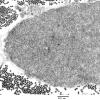

PERIPHERAL NEUROPATHY

5 AXONAL REGENERATION (6)